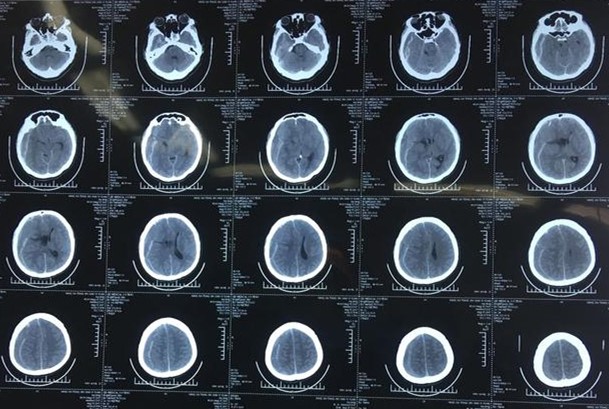

8月16日上午,我们在宁夏吴忠市同心县医院义诊。来自北京天坛医院神经外科的髙之宪主任接诊了一位剧烈头痛、左侧肢体不全偏瘫的患者。经头颅CT检查,发现“巨大右额颞顶硬膜下血肿”,已出现脑室受压,中线移位,大脑镰下疝,需要紧急行“硬膜下血肿钻孔清除术”,否则病人有死亡的危险。